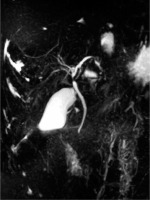

Ambulatory performed laboratory investigation confirmed increases in ALT (1084 U/l) and AST (1543 U/l) activity levels, as a result of which the boy was re-admitted to the hospital. Physical examination showed conjunctival icterus. Laboratory tests revealed increased levels of ALT (605 U/l), AST (1040 U/l), GGT (47 U/l), total bilirubin (2.55 mg/dl) and direct bilirubin (1.99 mg/dl), bile acids (364 µmol/l), as well as serum IgG (17.1 g/l), hypergammaglobulinaemia (23.9%), deranged coagulation profile (activated partial thromboplastin time 35 s, norm: 21.1-32 s, prothrombin time 15.7 s, norm: 10.4-14 s, fibrinogen 94 mg/dl, norm: 200-360 mg/dl, antithrombin 52%, norm: 80-120%) and positive ASMA (1 : 40). Ultrasonography of the abdomen showed only a small volume of pelvic free fluid. Doppler ultrasound of the hepatic vessels showed a dilated portal vein (14 mm) without other abnormalities at the level of the hepatic veins. The patient was further investigated with magnetic resonance cholangiopancreatography (MRCP), which demonstrated heterogeneous liver enhancement with an increased T2 signal predominantly in the left hepatic lobe, multifocal stricturing and dilation of intrahepatic and extrahepatic bile ducts (Fig. 1).

Fig. 2